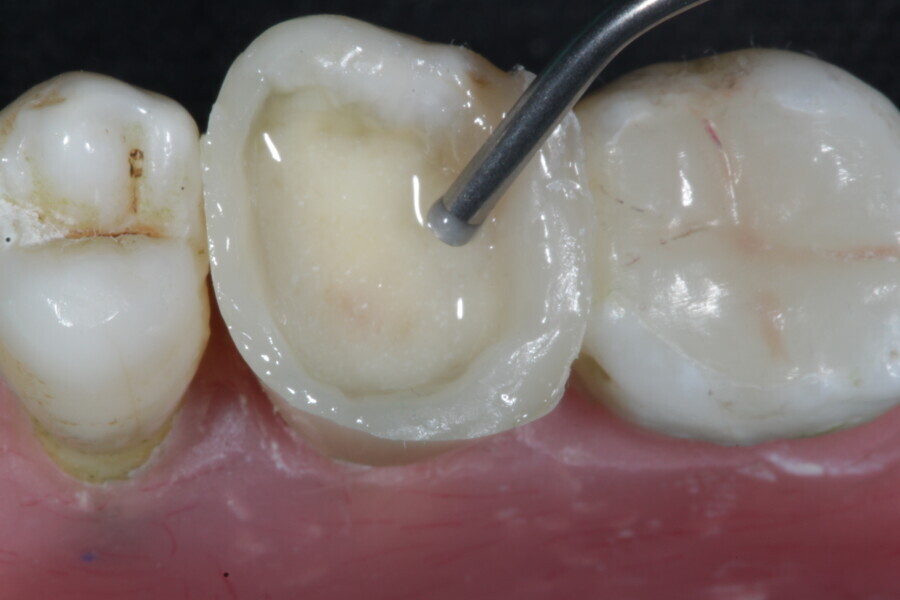

1. direct restoration using a fibre-reinforced flowable composite and membrane cube after endodontic treatment (Figs. 21–35); and

1. restoration reinforcement of a vital tooth with a fibre-reinforced flowable composite and membrane (Figs. 36–45).

Example 3—Restoration reinforcement of a vital tooth with a fibre-reinforced flowable composite and membrane.